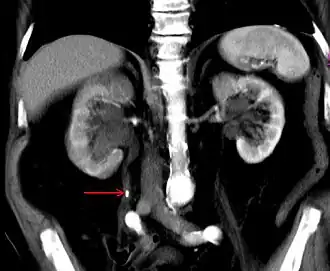

Stein im rechten Harnleiter (Pfeil), mit Harnaufstau. Computertomografie mit Kontrastmittel